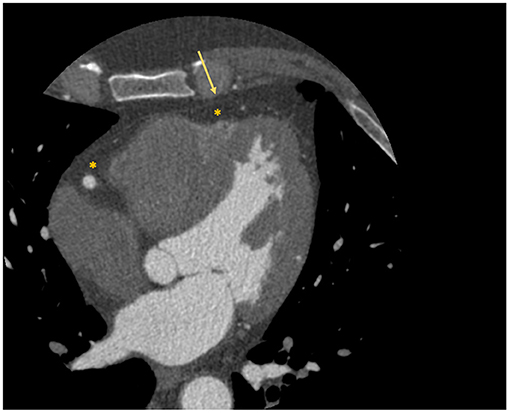

Not all coronary lesions imply the same cardiovascular risk. In particular, the detection of prevalent fibrotic composition and other specific plaque features at CCTA (Figure 5) have been associated with an increased risk of cardiovascular events (83). These high-risk features are represented by spotty calcifications, positive remodeling, low attenuation, and the napkin-ring sign (NRS) (83).

Figure 5

High risk features of coronary artery plaques. The figure shows clinical examples of high-risk plaque feature. (A) Depicts an example of a Napkin-ring sign. The asterisk identifies the hypodense necrotic core; the arrow identifies the hyperdense ring-like thin cap. (B) Depicts a high-risk coronary plaque with spotty calcifications and low attenuation (i.e., attenuation <30 HU). (C,D) Depict a coronary artery plaque with positive remodeling (i.e., a positive ratio between diameter of the vessel outside the plaque and its internal diameter) in short and long axis, respectively.